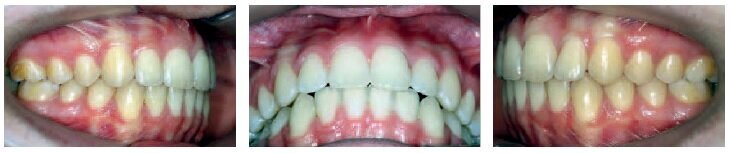

A long appointment was scheduled to—if all went well—remove the appliances and put a retainer in place. The day of the visit, the decision was made to proceed.

When I announced that the treatment would be completed that day, the patient and his parents had quite a memorable reaction: “Already? It went so fast! Thank you! He is going to have the best summer break!”

The results, although not perfect, were remarkable. The end-of-treatment records clearly show good tissue quality (periodontal and root integrity), undoubtedly thanks to the use of minimal force with long rest periods, a minimal number of archwires, and bonding which allowed for continuous improvement throughout the entire treatment, from beginning to end.